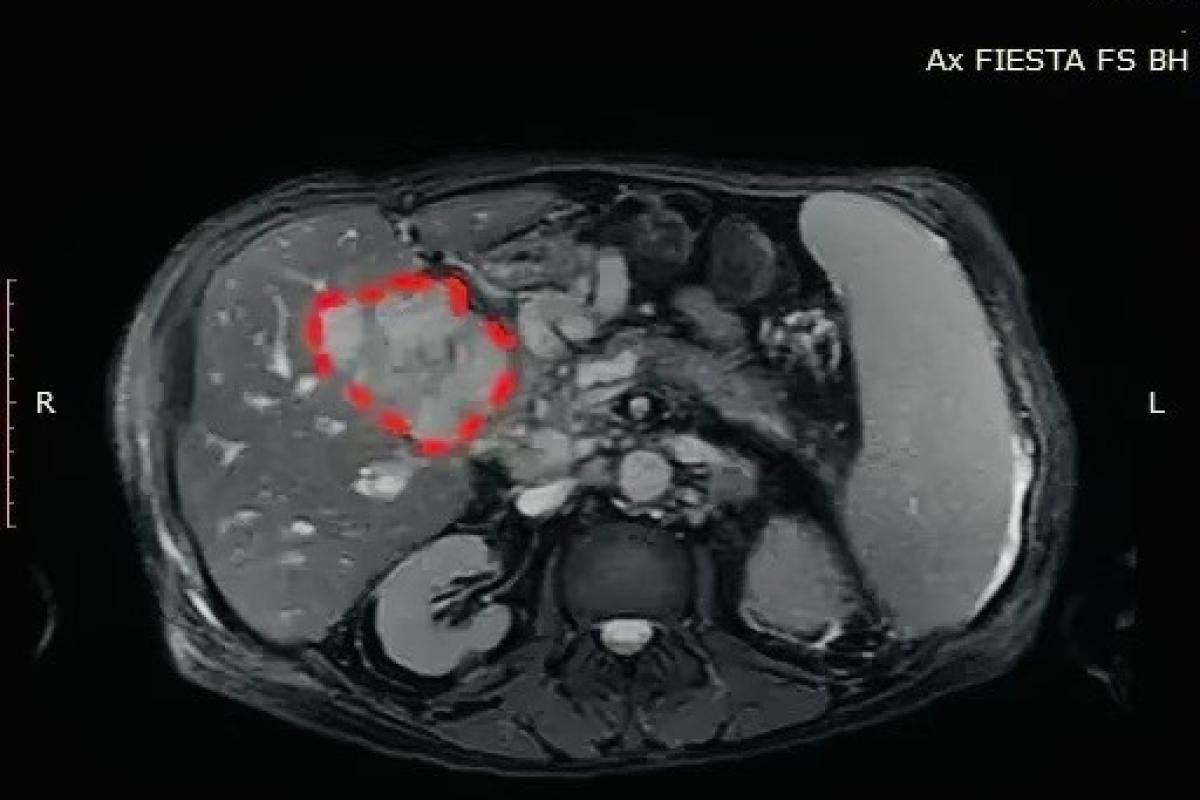

Мужчина поступил в областную клиническую больницу с жалобами на интенсивную боль в животе, повышение температуры и выраженную слабость. По итогам обследования медики установили, что в печени и желчном пузыре образовалось скопление гноя. Состояние осложнялось отеком окружающих тканей, что создавало риск повреждения важных протоков и развития сильного кровотечения при проведении хирургического вмешательства.

Операцию выполнили под местной анестезией с использованием ультразвукового контроля. Через прокол кожи и ткани печени врачи получили доступ к очагу воспаления и удалили около 150 миллилитров гноя. После проведенной процедуры температура у пациента снизилась, болевой синдром исчез.